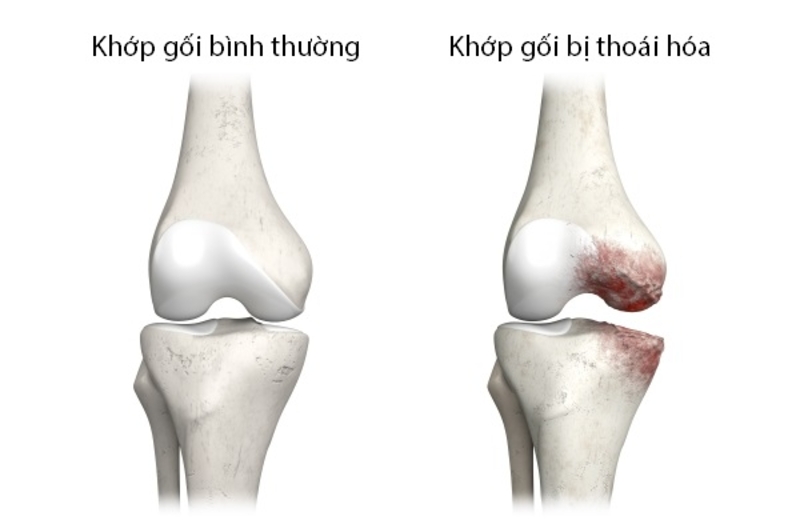

Thoái hóa khớp gối là hậu quả của quá trình cơ học và sinh học làm mất cân bằng giữa tổng hợp và hủy hoại của sụn và xương dưới sụn. Sự mất cân bằng này có thể được bắt đầu bởi nhiều yếu tố, bao gồm:

Biểu hiện cuối cùng của thoái hóa khớp gối là sự biến đổi hình thái, sinh hóa, phân tử và cơ sinh học của tế bào và chất cơ bản của sụn dẫn. Từ đó, dẫn đến nhuyễn hóa, nứt loét và mất sụn khớp, xơ hóa xương dưới sụn, tạo gai xương và hốc xương dưới sụn. Bệnh thường gặp ở nữ giới, chiếm 80% các trường hợp thoái hóa khớp gối.

Thoái hoá khớp gối có mấy độ? Hình ảnh minh họa thoái hóa khớp gối (Ảnh internet)